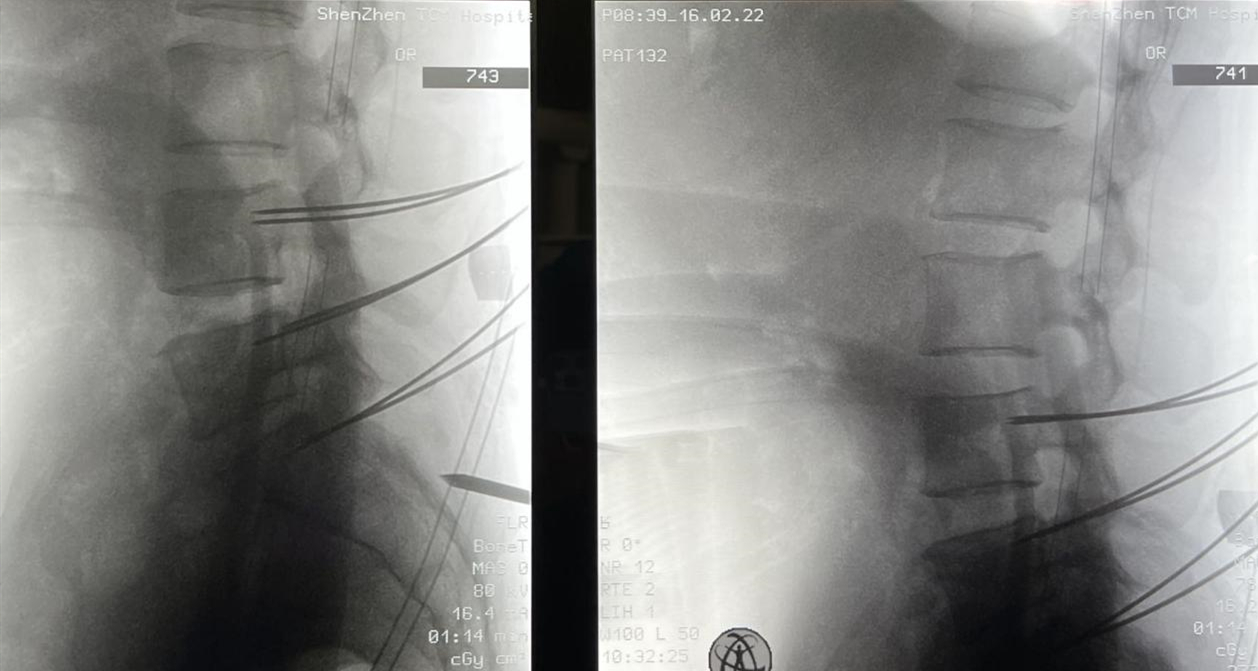

术中照片

在骨科手术机器人的辅助下,通过术中3D影像图像进行精准置钉路径定位规划,手术团队结合既往开放手术的经验,顺利在椎弓根置钉通道完成精准置钉,螺钉及走行位置满意,然后再行融合技术。术后患者症状得到有效缓解。借助天玑III骨科手术机器人的辅助,精准、高效地完成了手术,手术出血不到150ml,术后生命体征平稳,双下肢感觉、运动正常,脊柱序列恢复满意。